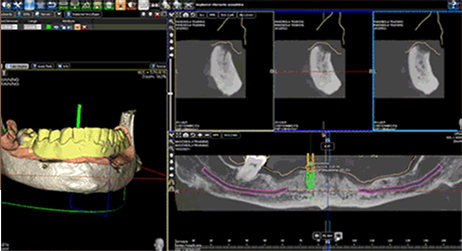

数字化种植是利用计算机图形图像技术,根据口内CT扫描数据以及光学扫描数据在计算机上重建患者颌骨立体模型,医生以此为基础,确定患者种植体嵌入位置、数量、种植深度、角度等,生成科学、精准的导板设计方案,将种植设计准确地转化到手术操作中,最后配上数字化种牙手术专用的手术工具、结合患者自身的情况制作修复体,完成种植治疗。

- 口内模拟种植,避开神经血管,设计种植方案;通过CAD/CAM激光扫描和CBCT检测等, 在计算机上重建患者口腔三维立体模型,凭借由打印技术制作的种植导板对手术全程的精准把控,减少手术时间及手术创伤,实现对缺牙的修复。

- 导板技术就犹如地图,精准的为医生指引着方向,精确到 0.1毫米。

- 利用数字化技术,术前充分评估患者条件,设计合适的种植体数量、型号和具体位置,保证负重的成功及植体稳定性,配合使用打印种植导板精确实现设计的种植方案,同时缩短手术时间,减少手术创伤,让患者有更好的体验。

在导板辅助下可避免医生经验误差,掌控种植角度和深度,减少创伤,有效避开神经、血管等危险部位。